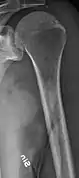

The diagnostic examination of a person with suspected multiple myeloma typically includes a skeletal survey. This is a series of X-rays of the skull, axial skeleton, and proximal long bones. Myeloma activity sometimes appears as "lytic lesions" (with local disappearance of normal bone due to resorption) or as "punched-out lesions" on the skull X-ray ("raindrop skull"). Lesions may also be sclerotic, which is seen as radiodense.[70] Overall, the radiodensity of myeloma is between −30 and 120 Hounsfield units (HU).[71] Magnetic resonance imaging is more sensitive than simple X-rays in the detection of lytic lesions, and may supersede a skeletal survey, especially when vertebral disease is suspected. Occasionally, a CT scan is performed to measure the size of soft-tissue plasmacytomas. Nuclear Medicine Bone scans are typically not of any additional value in the workup of people with myeloma (no new bone formation; lytic lesions not well visualized on nuclear bone scan).